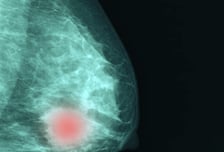

"유방암 맞춤형 치료 기대" 환자별 재발 예측하는 새 연구법 나왔다

국내 여성암 발생 1위를 달리는 유방암은 환자가 지닌 '인자' 유무에 따라 여러 아형(subtype)으로 분류된다. 유전자를 이용한 첨단 검사법이 활용되면서, 분류에 따른 치료 방향이 더욱 정밀해지고 있다. 유방암을 분류하는 전통적인 방식으로는 먼저 '호르몬수용체' 유무에 따라 양성·음성을 대분류한 후, 'HER2'라는 인간 표피 성장 인자 수용체 2형 단백질(암세포 표면에서 HER2가 무한 증식을 일으키면 문제가 될 수 있음)의 유무로 나눴다. 하지만 최근엔 호르몬수용체를 지니고(양성) HER2 단백질이 없는 그룹도, 'HER2 저발현 그룹(HER2-Low)'과 'HER2 음성(HER2-zero)' 그룹으로 세분하는 추세다. 그런데 HER2 저발현 그룹이 HER2 음성 그룹보다 유방암 재발 예측점수(RS : Recurrence Score)가 높다는 최신 연구 결과가 발표됐다. 쉽게 말해 HER2 라는 단백질이 없는 경우보다 조금 발현됐을 경우, 유방암 재발 확률이 높아진다는 것이